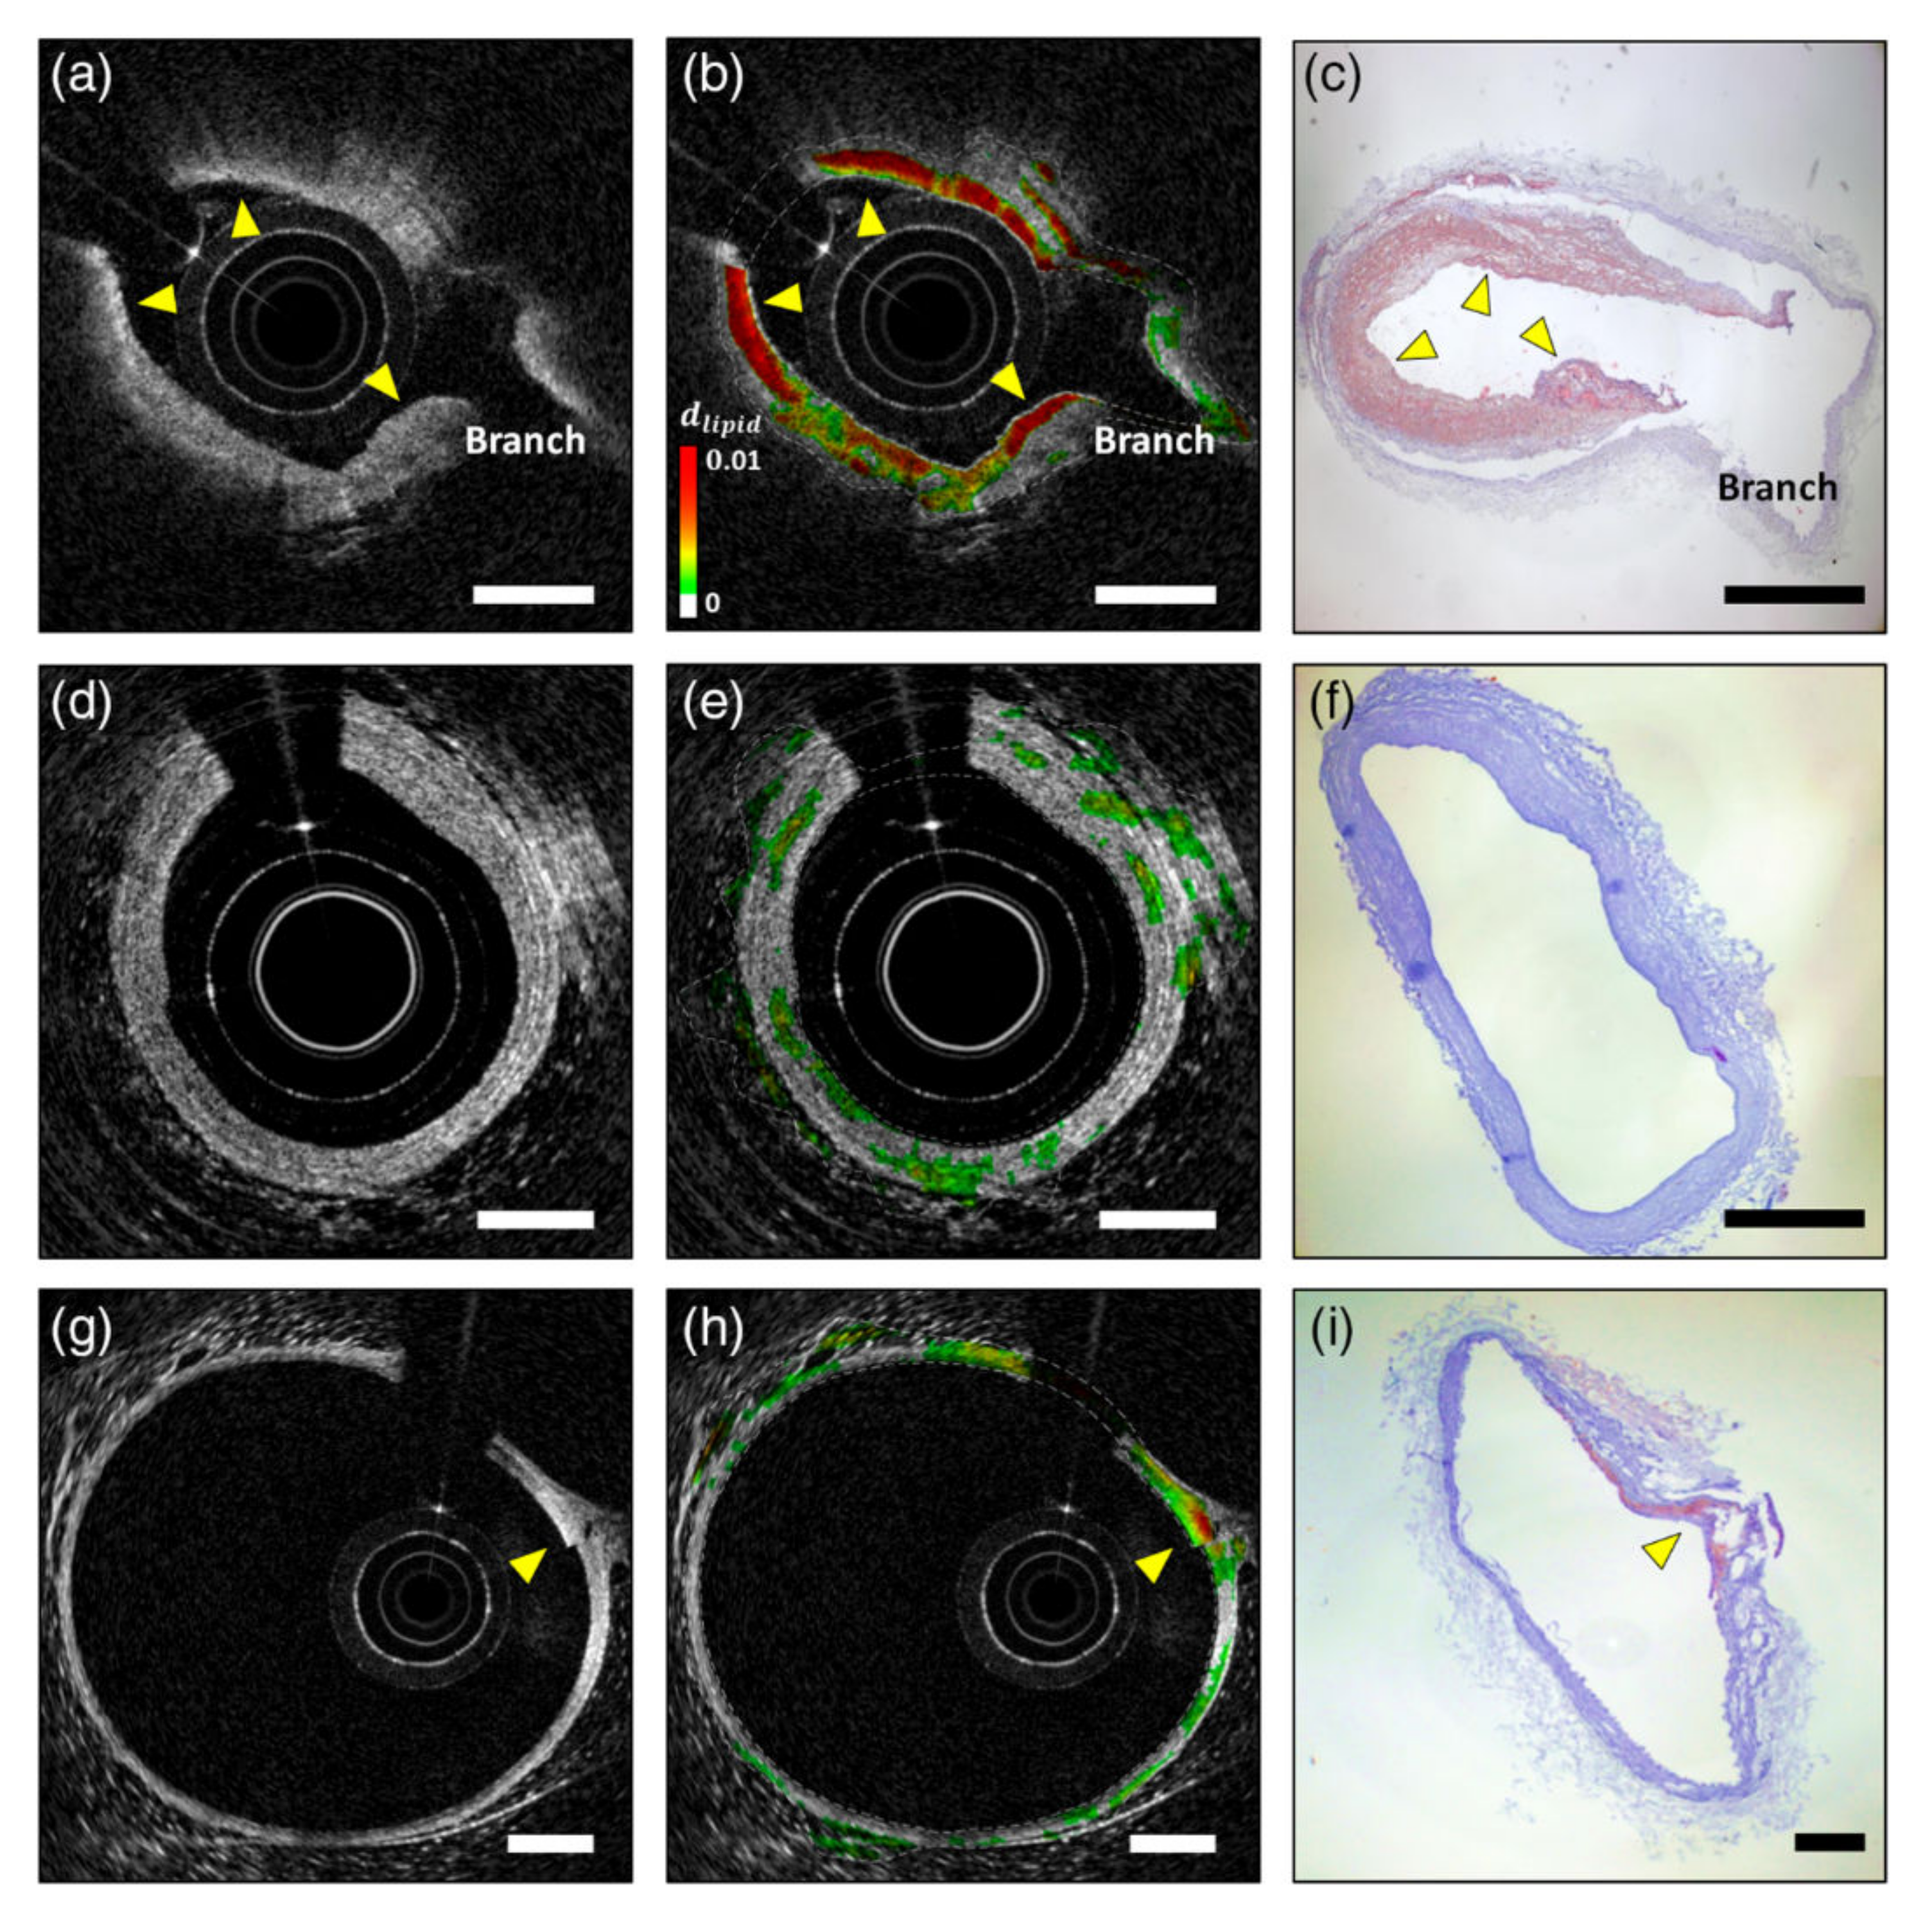

- Hyeong Soo, N.; Joon Woo, S.; Sun-Joo, J.; Jae Joong, L.; Wang-Yuhl, O.; Jin Won, K.; Hongki, Y. Characterization of lipid-rich plaques using spectroscopic optical coherence tomography. J. Biomed. Opt. 2016, 21, 1–9. [Google Scholar] [CrossRef]